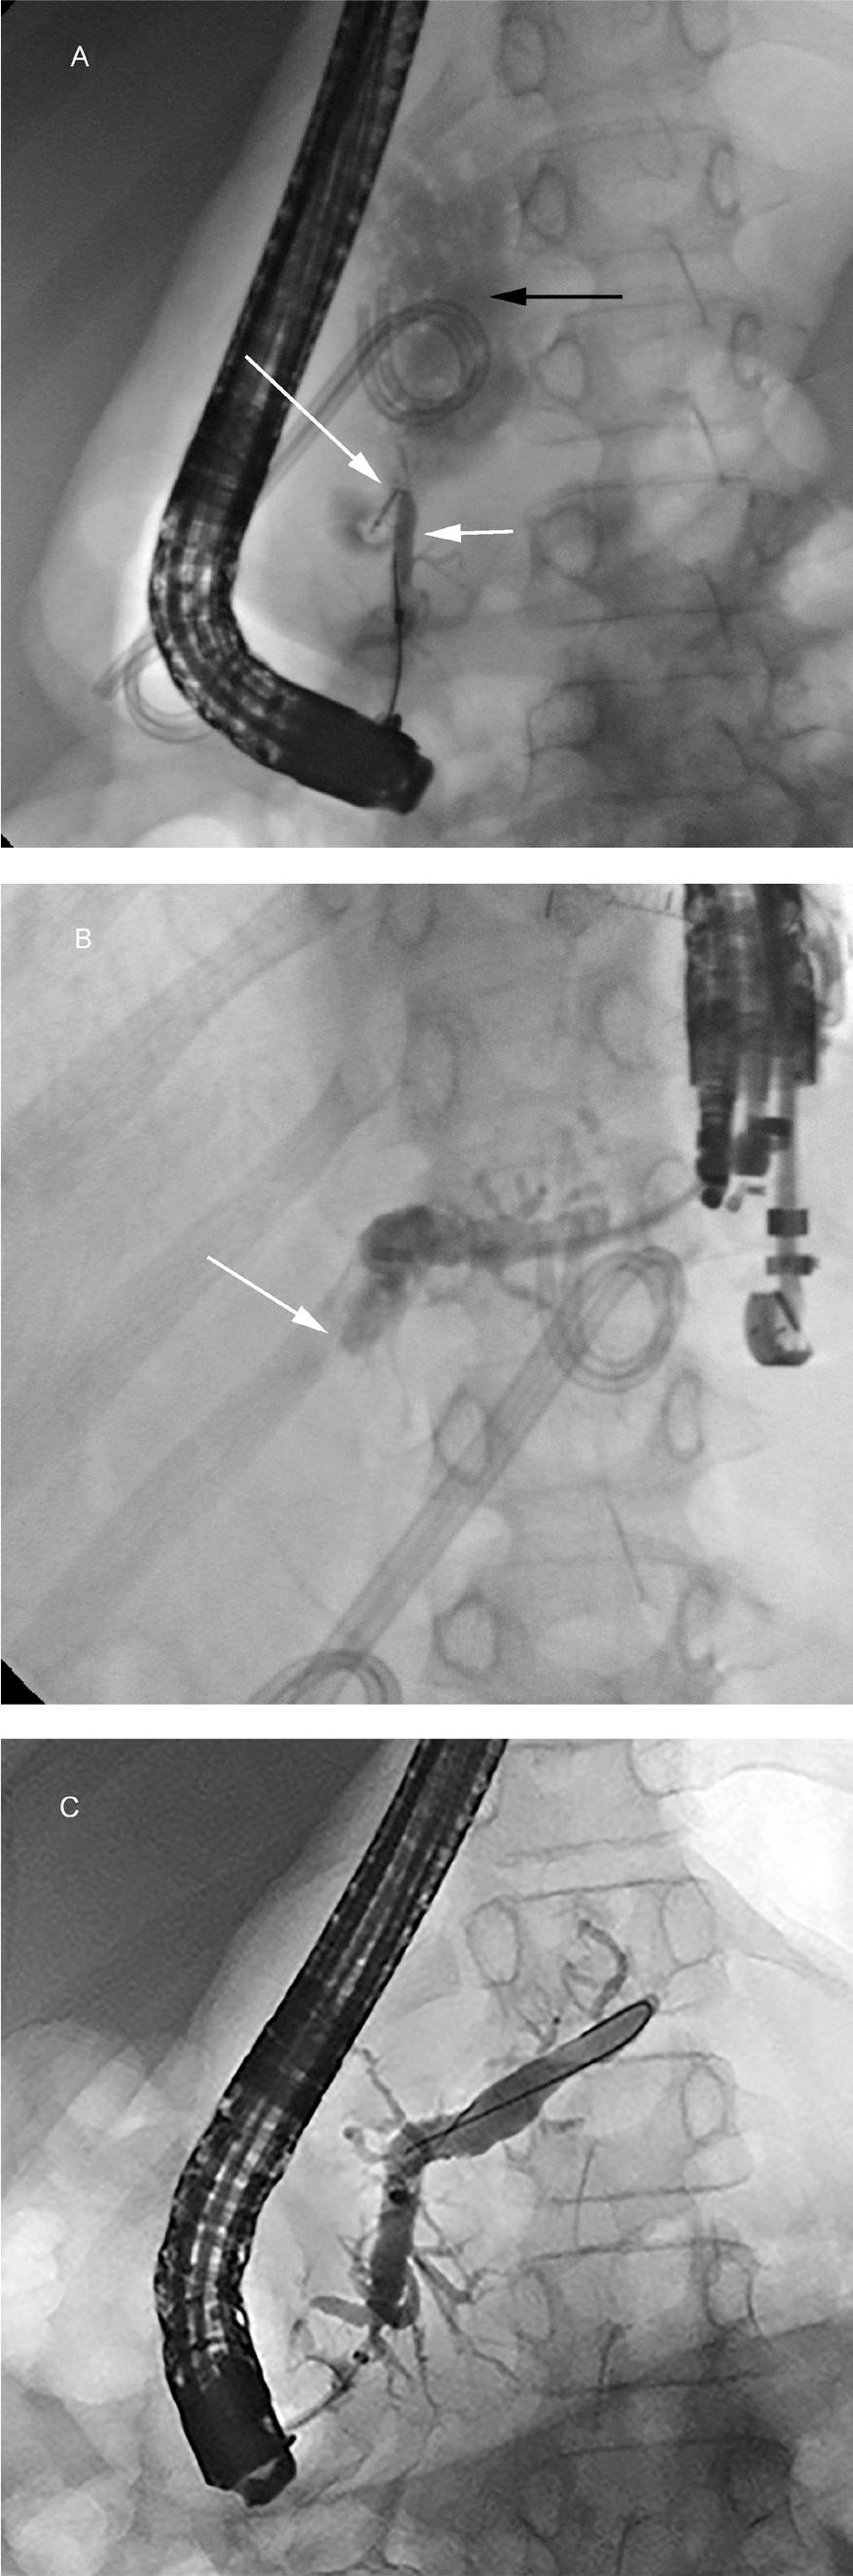

Figure 3